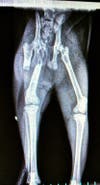

I have attached two pictures with this blog post. Please take a minute to click and look at them both.

1. An xray of a cat pulled by a local rescue was held at MADACC for at least seven days with this fracture without treatment. Apparently they knew of the injury but did not treat it and when she was finally released to a rescue, she was sent with antibiotics but no pain medication. The rescue immediately took the cat to their veterinarian who took this xray and recommended that the cat have emergency surgery to repair the broken femur.